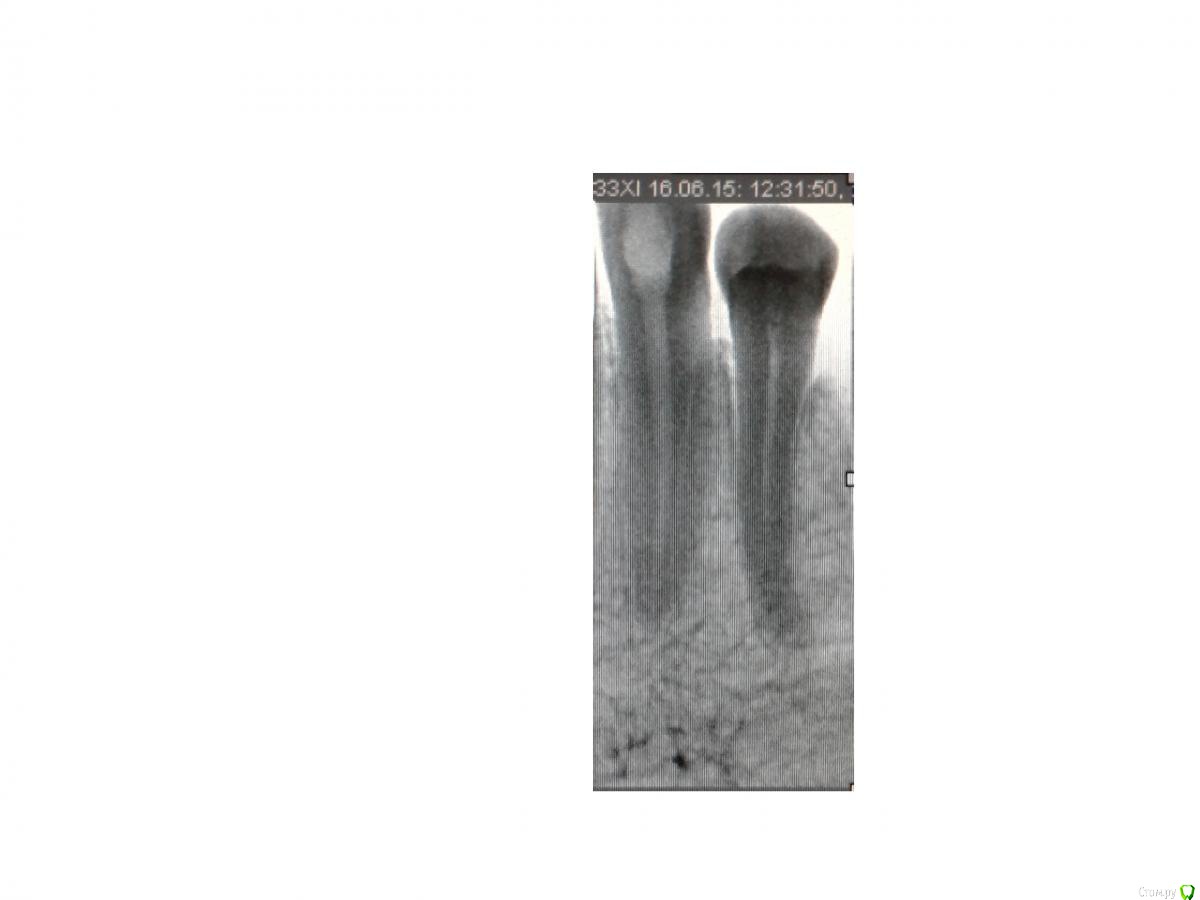

mariskus71 Опубликовано 25 августа, 2015 Автор Поделиться Опубликовано 25 августа, 2015 (изменено) Если Вы об этом - то это не канал , а контуры костной перегородки между этим и соседним зубом. А снимки выкладывайте, посмотрим.Спасибо Вам большое,сняли груз с души,а то я уж думала,что дополнительный канал не запломбировали.Выкладываю снимки.Первый снимок был сделан после пломбировки временным каласептом.Второй перед пломбировкой прошли канал и нашли дополнительный.А на последнем врач отметил непонятные участки (со вторым я поняла,а вот с первой цифоркой то же непонятно)Спасибо Изменено 25 августа, 2015 пользователем mariskus71 Ссылка на комментарий

St. Опубликовано 25 августа, 2015 Поделиться Опубликовано 25 августа, 2015 Пожалуйста) По снимку с инструментами всё хорошо. По тому который после пломбировки - тоже.Что врач хотел отметить - не знаю.Как сейчас ведет себя зуб? Неприятные ощущения уменьшаются? Ссылка на комментарий